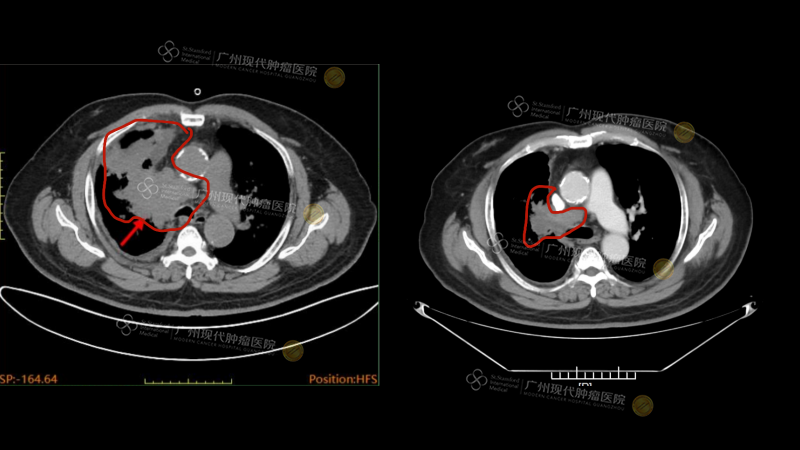

Setelah menyelesaikan siklus pengobatan pertama, Prospero tidak lagi memerlukan alat bantu oksigen, dan pernapasannya menjadi lancar. Setelah tiga siklus pengobatan, tumornya mengecil secara signifikan (dinilai sebagai PR): CT scan sebelum pengobatan menunjukkan ukuran tumor sebesar 81×59×78mm, dan setelah dua kali tindakan intervensi, CT scan ulang menunjukkan ukuran tumor mengecil menjadi 47×32mm.